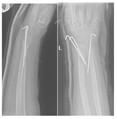

(2)经皮克氏针组:折顶复位后,在C型臂X线机透视下见骨折对位良好。助手维持牵引位置,根据骨折的类型、移位方向选择桡骨茎突近侧、桡骨背侧结节近侧作为进针点交叉或平行打入2枚克氏针(美国施乐辉公司生产,直径1.6 mm或1.9 mm),通过骨折部位髓腔后再穿出近端骨皮质。尺骨骨折端采用1枚克氏针斜行固定(图2)。